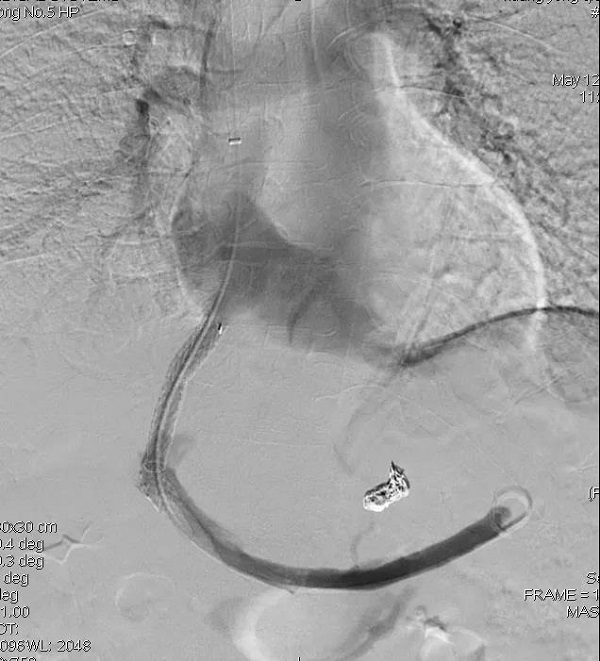

|     近日,南充市高坪区人民医院介入中心成功完成2例TIPS(经静脉肝内门-体静脉支架分流术),彻底解除患者食管胃底静脉曲张破裂顽固性出血的困扰。 病例介绍 病例1   患者何女士,70岁,因剑突下伴双侧季肋区不适、呕血1小时于2021年4月27日入住全科医疗科,入院诊断:1.肝硬化,上消化道出血;2.食管胃底静脉曲张。既往有冠心病、心绞痛、高血压、糖尿病及乙肝病史。曾多次因大量呕血住院治疗(2014年行“脾切除术及贲门周围血管离断术”,2019年行“内镜下食管胃底静脉曲张套扎术”),不久后即复发呕血,最多出血量达200-300毫升。 病例2   患者黄某,男,66岁,因突发呕血2小时量约300ml于2021年4月30日入住全科医疗科,入院诊断:1.乙肝后肝硬化失代偿期;2.门静脉高压;3.食管胃底静脉重度曲张、破裂。既往有乙肝病史,长期呕血、解黑便、贫血,苦不堪言。 手术情况   针对患者病情,全科医疗科与介入中心经过会诊讨论、充分术前评估和准备,于5月2日、5月12日,介入中心主任廖歆副主任医师团队先后成功为两名患者实施TIPS,彻底解除食管胃底静脉曲张破裂顽固性出血。术后患者恢复良好,肝功能等各项指标恢复正常,贫血状况得以改善,现均已康复出院。 TIPS实施中 术前明显迂曲扩张的食道胃底静脉 术后曲张静脉已封堵 并重建门体分流通道   TIPS是血管介入手术中难度最大的四级手术之一,对于肝硬化导致的门静脉高压及相关并发症,该手术现已成为其主要的治疗方式。与外科门体静脉分流术相比,该手术具有创伤小,成功率高,降低门脉压力可靠,并发症少,能同时进行曲张静脉栓塞等优点。对于门静脉高压症所导致的顽固性腹水,也有显著的疗效。 03 TIPS操作流程   将穿刺套件经肝静脉穿刺肝内门静脉,用球囊进行分流道扩张,置入覆膜支架覆盖穿刺通道,人为建立门体分流通道。   食道胃底静脉曲张,采用胃冠状静脉栓塞。   门静脉系统血流经门体分流通道进入下腔静脉,门静脉压力显著降低,出血、呕血彻底解除。术后予颈静脉穿刺点压迫,病人在8小时后就可下床自由活动。 介入中心简介   南充市高坪区人民医院介入中心现有专业技术人员15人,其中高级技术职称5名,中级技术职称7名,初级技术职称3名。拥有美国GE数字减影血管造影机(DSA),进行胸部、腹部、四肢、头颅和外周血管造影和介入治疗,具有实时数字电影采集、各种血管测量分析软件和后处理软件,图像质量好,存储容量大,射线剂量低,操作灵活方便,技术含量高。   介入诊疗项目:   1.实性肿瘤血管灌注化疗栓塞术,如肝癌、肺癌、胃肠癌、肾良恶性肿瘤、胰腺癌、转移性肿瘤等。   2.冠状动脉造影与支架植入、心律失常介入治疗。   3.消化道出血、咯血、外伤性脏器破裂出血等疾病血管栓塞术。   4.下肢动脉、内脏动脉造影、狭窄或闭塞性动脉的介入治疗(球囊扩张、支架置入)。   5.深静脉血栓、髂压综合症的介入治疗,下腔静脉滤器置入、肺动脉溶栓。   6.产后出血、瘢痕妊娠、前置胎盘、妇产科肿瘤、输卵管阻塞介入治疗。   7.全脑血管造影、颅内动脉及颈动脉狭窄、动脉瘤、急性脑梗死介入治疗。   8.胆道梗阻、肠梗阻的介入治疗。   9.肝硬化门静脉高压、消化道静脉出血的介入治疗。脾功能亢进介入治疗。   10.消化道疾病球囊扩张术、支架置入术、胃肠营养管置入术。   11.CT引导下穿刺活检、囊肿硬化治疗、脓肿引流。   12.椎体成形术、疼痛治疗等。   13.动静脉内瘘狭窄再通术。   咨询电话(专科楼1楼):   0817-3313573 |